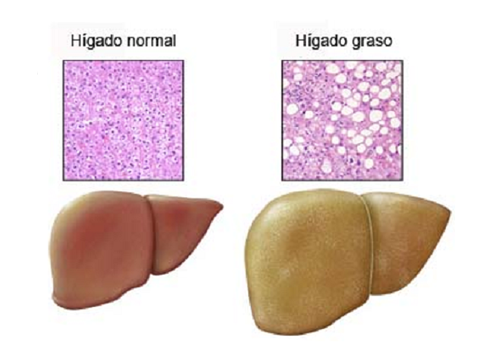

El “hígado graso” es realmente la esteatosis hepática y es una condición reversible que puede desaparecer si se modifican los hábitos alimenticios. No es algo normal, pero no es tan grave si se trata a tiempo.

Este problema se presenta en las personas cuyo nivel de grasa en este órgano representa entre 5 y 10% del peso hepático, generalmente son los enfermos de diabetes o las personas mayores de 50 años. Existen dos tipos: